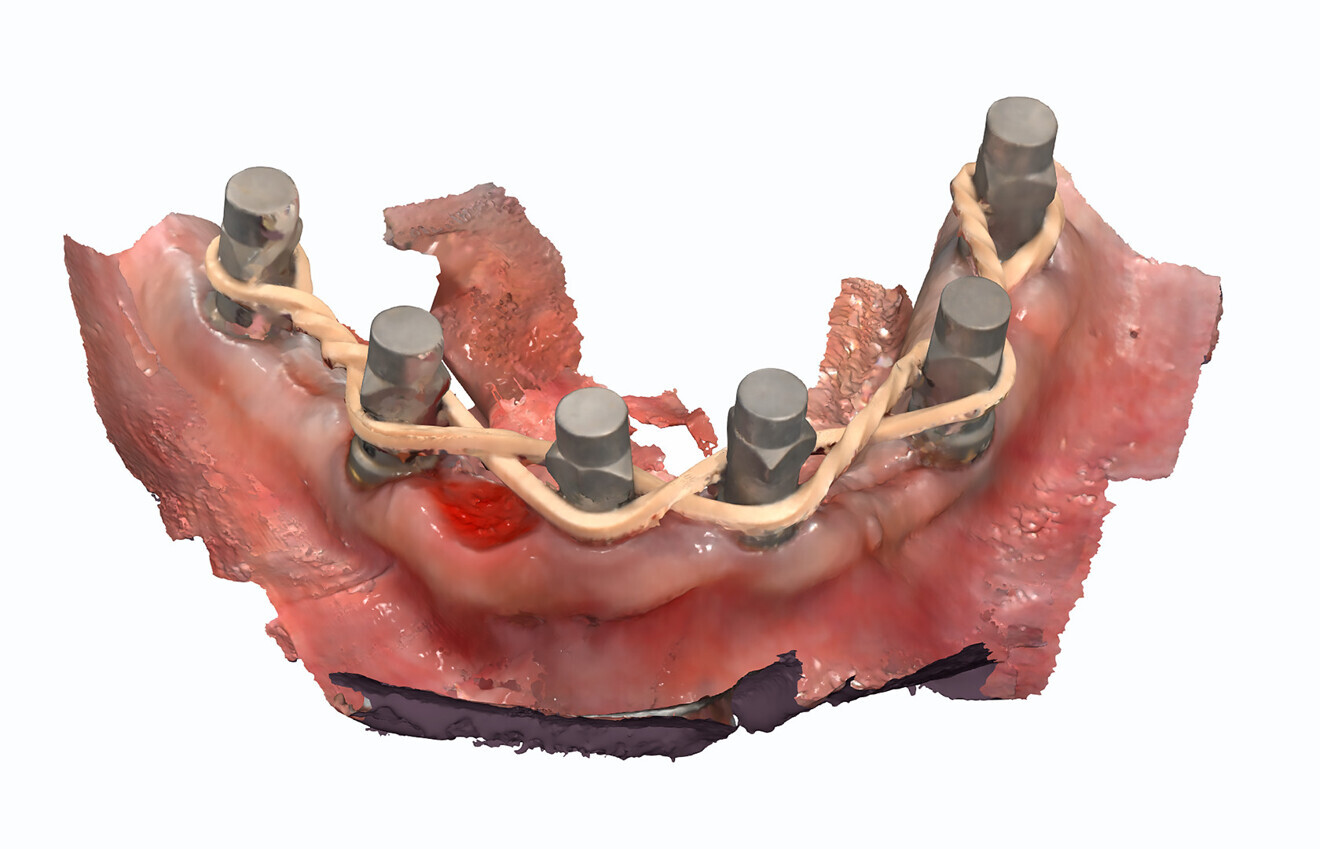

The analogue–digital process utilises MUA-compatible scan bodies (OptiSplint) designed to incorporate an aluminium mesh frame (Fig. 3a) that can be customised chairside (with the snipping tool included) as required by the intra-oral location of the implants. This mesh frame comes in small and large sizes to accommodate various mouth sizes and MUA–implant positions. The workflow involves inserting the scan bodies on to the MUAs intra-orally (Fig. 3b). The proprietary scan bodies have extensions (Fig. 4) to allow the mesh to seat and rotate in close proximity to the extensions, which facilitate luting using a resin base material (STELLAR DC Acrylic, Taub Products). The structure can then be digitised by scanning intra-orally with an intra-oral scanner and extra-orally with an intra-oral scanner or desktop scanner. The bonded splinting of the scan bodies to the mesh frame allows for a simple uninterrupted scan path.

The Grammetry process provides the clinician with the fully digital benefits of photogrammetry while providing the capability to fabricate analogue models that can be articulated as part of the prosthetic design process represented by the clinical workflow (Fig. 5). Additionally, the Grammetry splint can be used as a model verification jig. The fully digital Grammetry process communicates to the dental laboratory the necessary records workflow to design and fabricate a full-arch prosthesis at a significantly reduced cost. For those who have 3D printers and wish to design and print the provisional prosthesis, a calibration device is included in the Grammetry kit. This device will ensure that the specific printer settings based on the resin used will achieve a passive fit.

After four months, the patient returned to complete the process of finalising the final prostheses. Final records were taken, including new digital scans and photographs. Photographs included the patient profile when smiling and not smiling as well as intra-oral occlusion. The digital scans included a facial scan acquired from the CBCT device, maxillary and mandibular soft-tissue scans using scan bodies (DESS), bite registration, an iJIG scan of the provisional restorations for tooth positions,3 photogrammetry (iCam4D, iMetric 4D) and Grammetry scans (Fig. 15). The Grammetry scans were scanned extra-orally with both the intra-oral scanner and an extra-oral desktop scanner (Medit T710) for comparison.